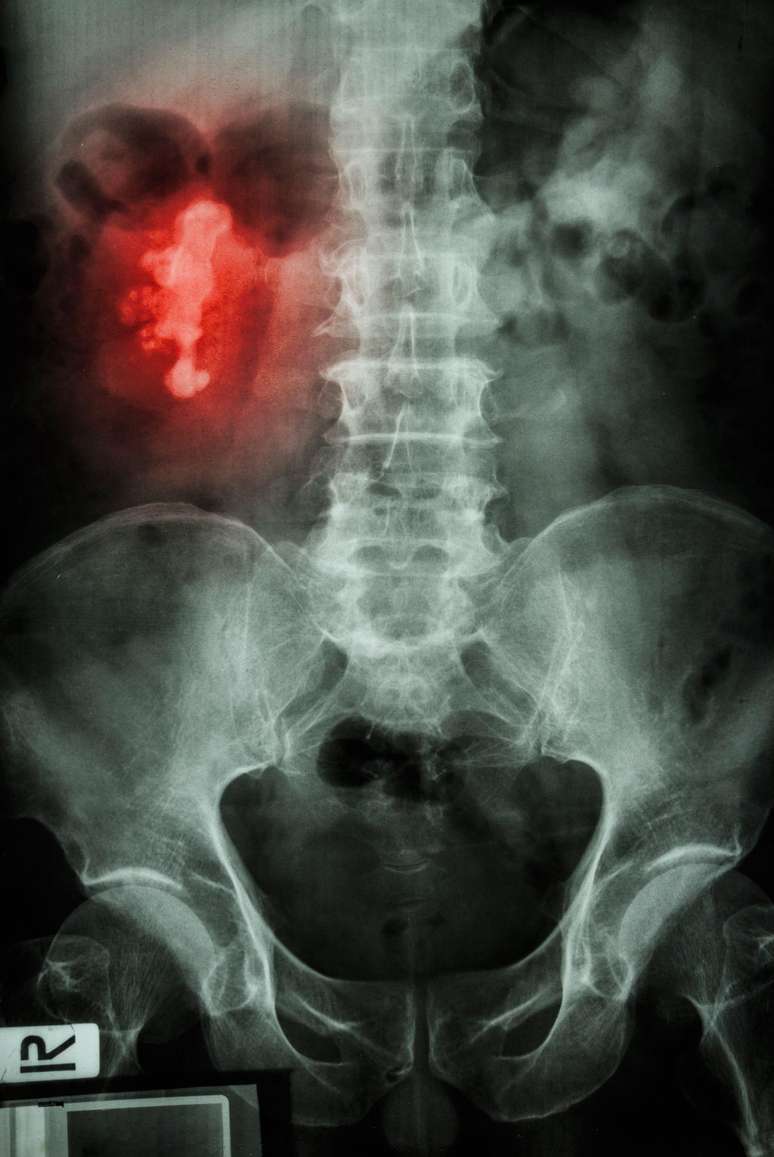

Eles também podem ter formas incomuns: se a pedra se acumular nos canais ramificados (cálices) do rim, ela pode ter o formato de um chifre de um cervo.

Por isso é conhecido como cálculo "chifre de veado".

Imagem de raio-x detecta uma pedra chifre de veado no rim direito de paciente

Foto: Getty Images / BBC News Brasil